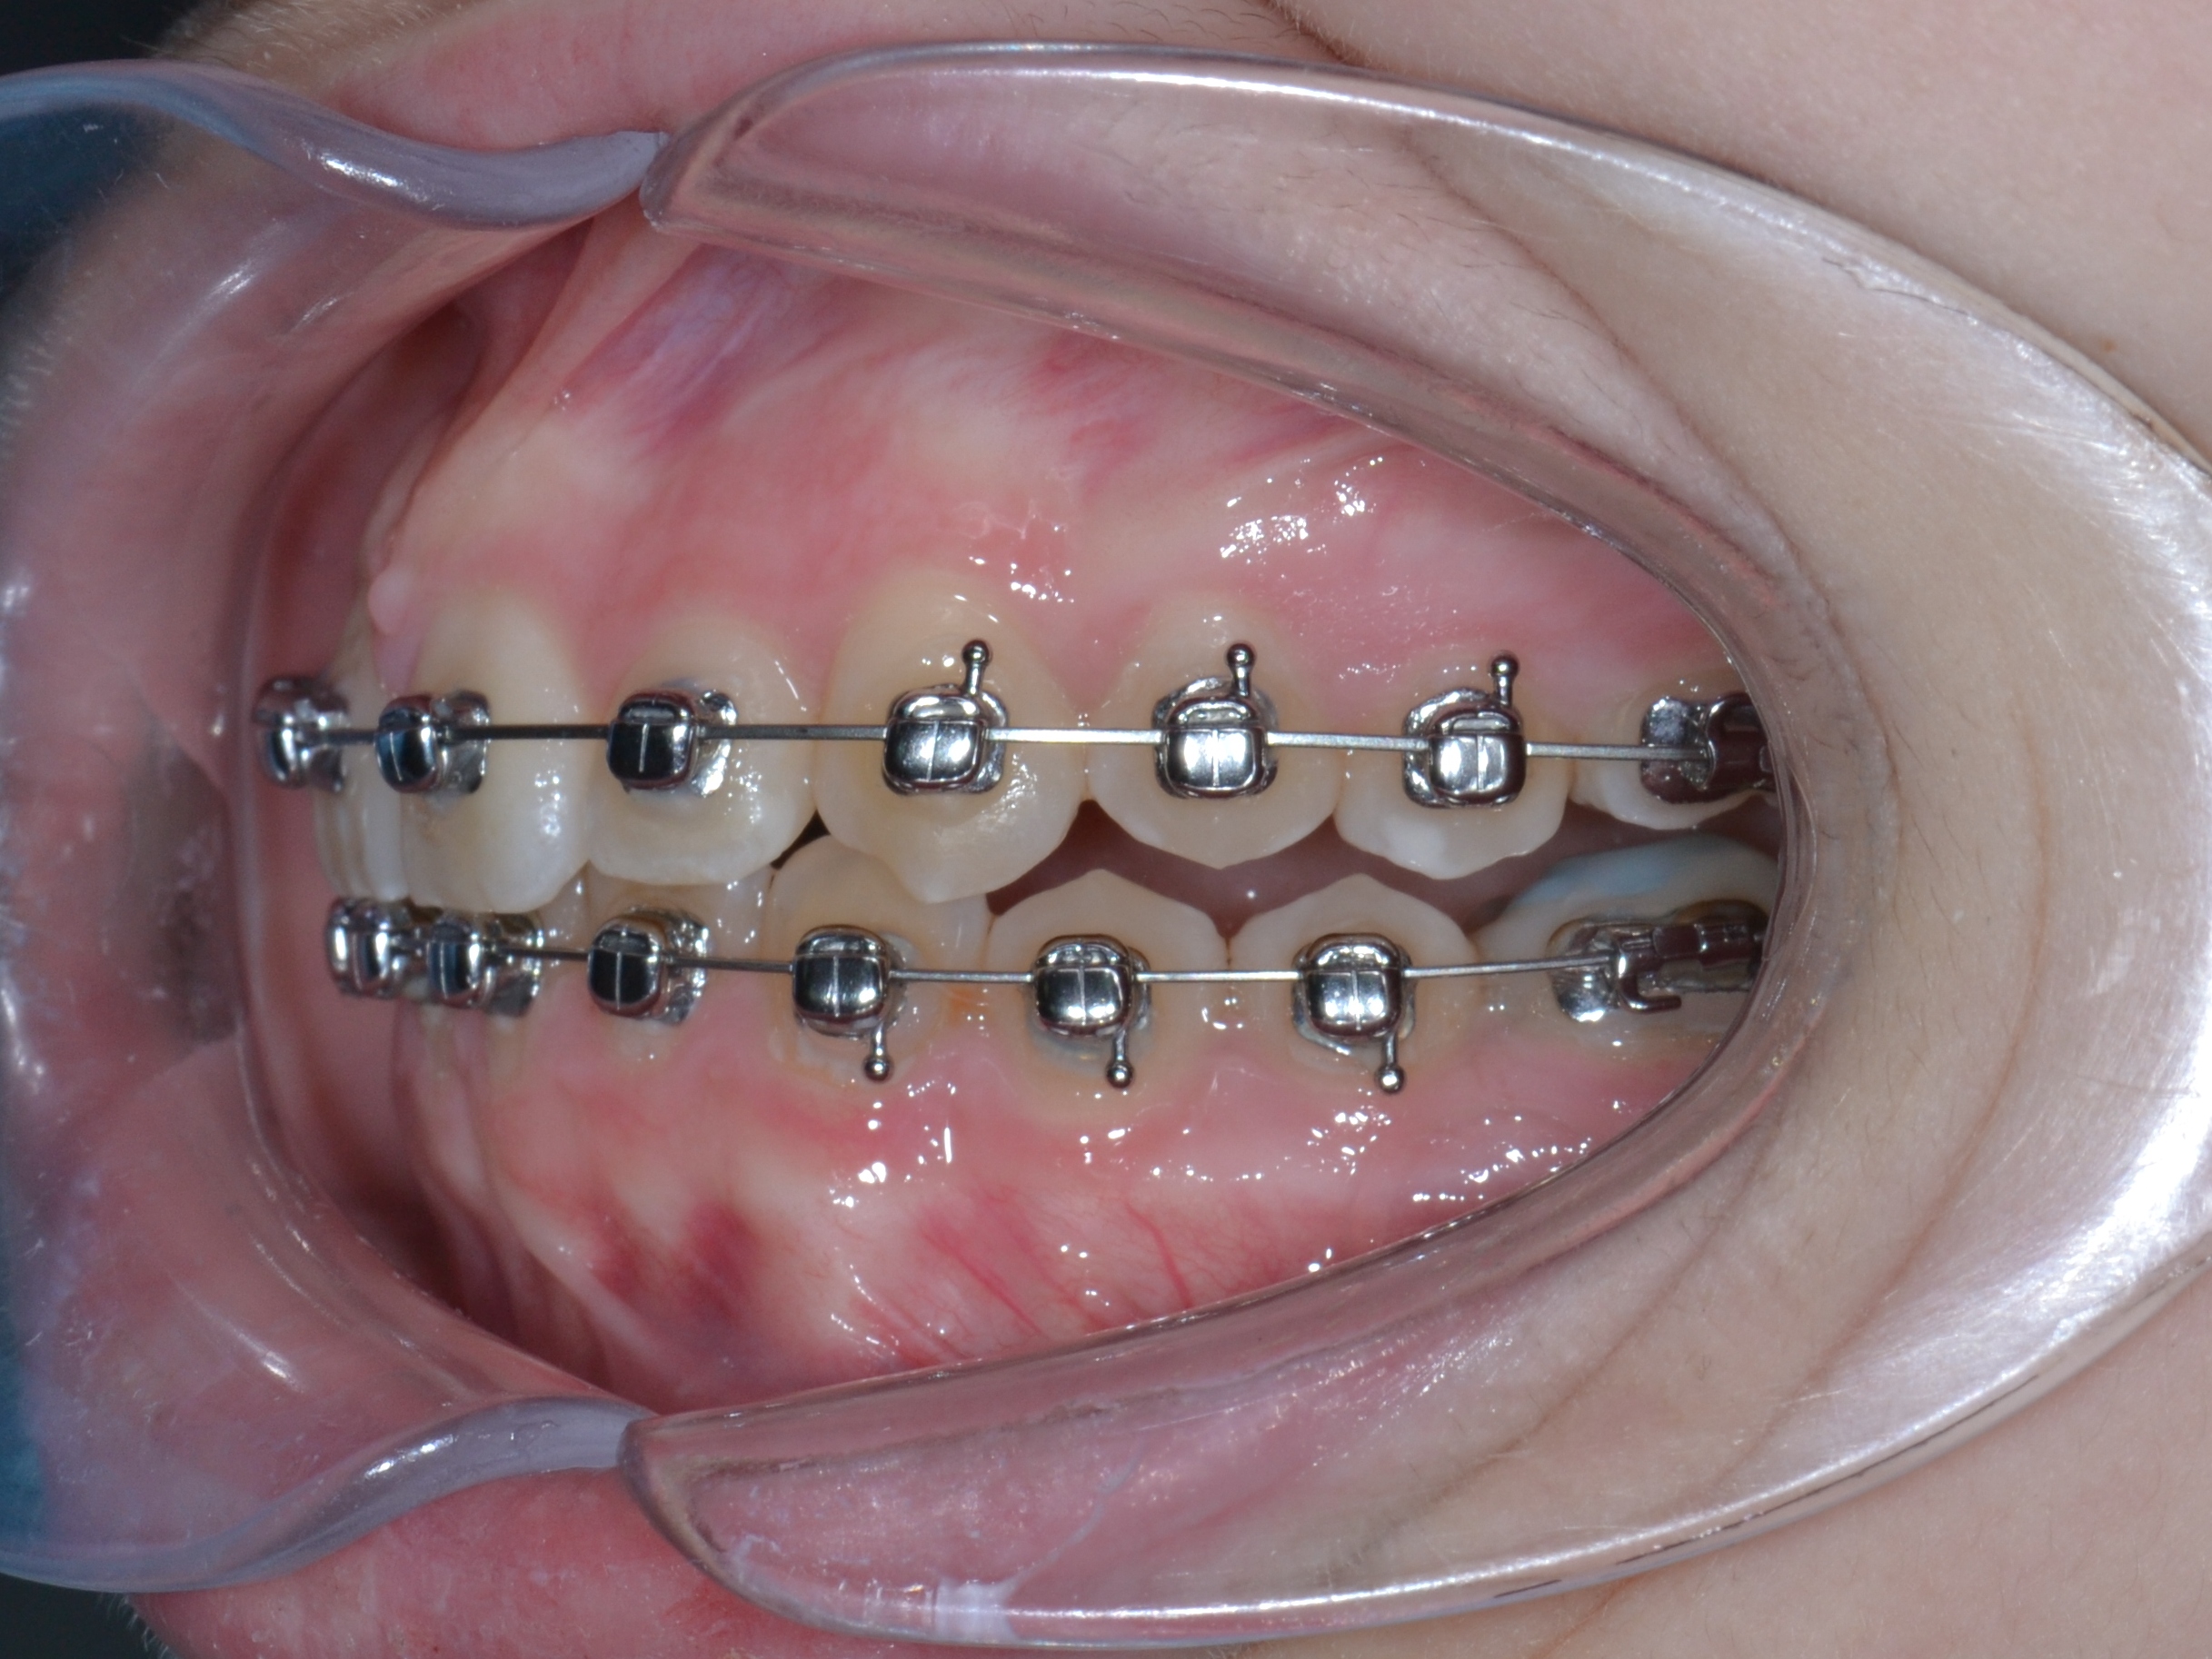

2

6 месяцев

Декабрь 2024 г.